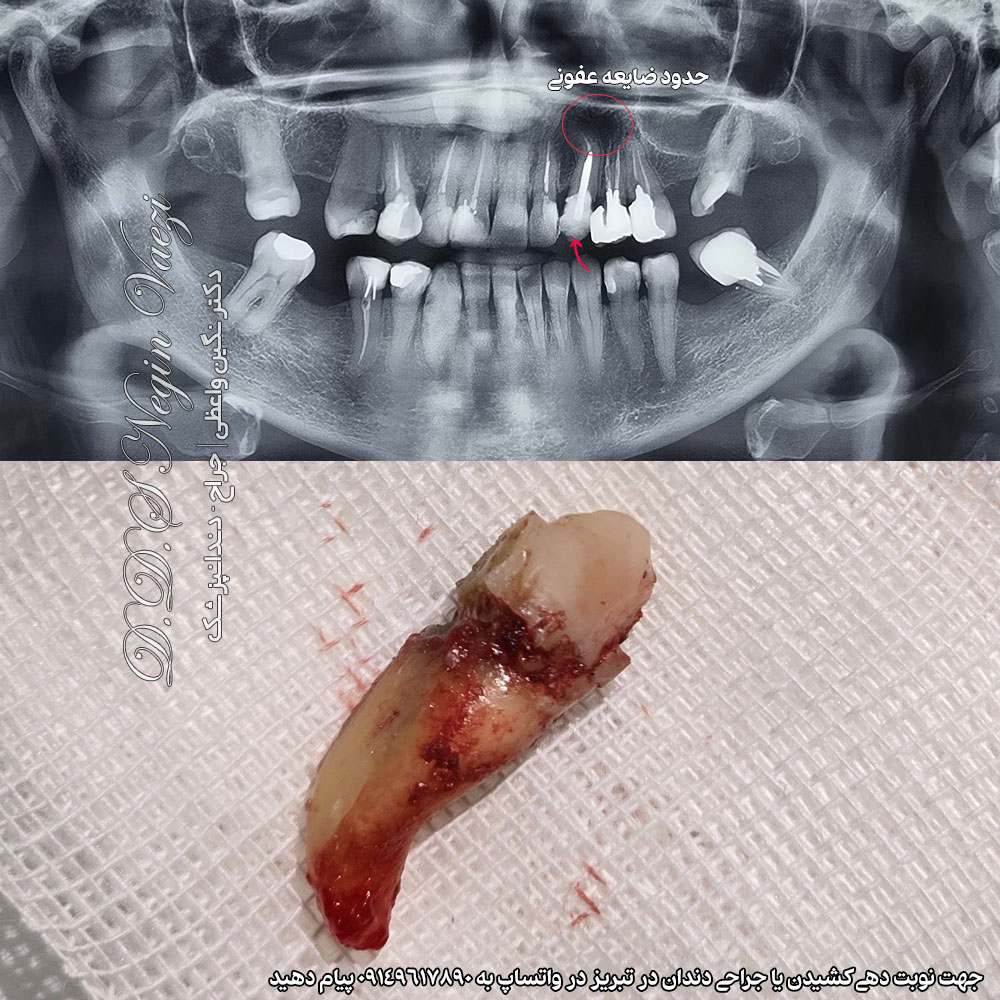

در این نمونه درمان انجام شده توسط دکتر نگین واعظی؛ دندان 3 (دندان نیش یا کانین) فک بالا سمت چپ به دلیل عفونت شدید و غیر قابل نگهداری بودن، خارج شده است. علت کشیدن دندان نیش بیمار این بود که ، علاوه بر عفونی بودن، امکان انجام درمان های محافظه کارانه دیگری را نداشت. بررسی بالینی و تصویر رادیوگرافی که در ادامه مشاهده خواهید کرد ، به وضوح عفونت را نشان می دهد.

عکس قبل و بعد کشیدن دندان نیش فک بالا سمت چپ

مطابق عکس رادیوگرافی زیر، ادامه حفظ دندان نیش بیمار می تواند منجر به گسترش عفونت و آسیب بیشتر به استخوان فک و دندان های کناری شود. بنابراین کشیدن دندان نیش بعنوان ایمن ترین و علمی ترین انتخاب درمانی انجام شد.

پس از خارج کردن دندان (بدون نیاز به جراحی) ، ضایعه عفونی به طور کامل کورتاژ شد و شستشوی دقیق ساکت دندانی برای پاک سازی بافت های آلوده انجام گرفت.در پایان، ناحیه بخیه زده شد تا شرایط مناسب برای ترمیم استخوان فراهم شود. پس از طی دوره بهبودی و پایدار شدن استخوان ، برنامه ریزی برای کاشت ایمپلنت به همراه بازسازی استخوان ناحیه (GBR) انجام خواهد شد تا بهترین نتیجه از نظر عملکرد حاصل گردد. در ادامه عکس قبل و بعد را مشاهده می کنید.